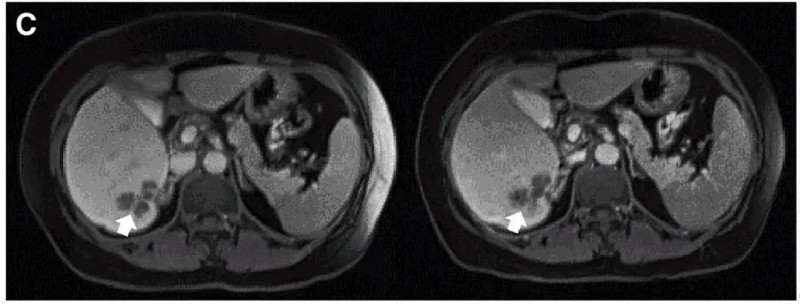

我国开展的一项“CEA靶向CAR-T细胞疗法治疗CEA阳性结直肠癌的I期临床试验(NCT02349724)”,结果振奋人心:10例既往治疗进展(PD)的患者中,7例治疗后达到病情稳定(SD)(肿瘤直径仅轻微变化),其中2例稳定状态持续超30周(7.5个月)。

值得一提的是,典型病例P10患者在接受DL4剂量CEACAR-T治疗后,MRI证实其肝内一处病灶明显缩小,左图为治疗前影像,右图为治疗4周后影像对比。

▲图源“Molecular Therapy”,版权归原作者所有,如无意中侵犯了知识产权,请联系我们删除